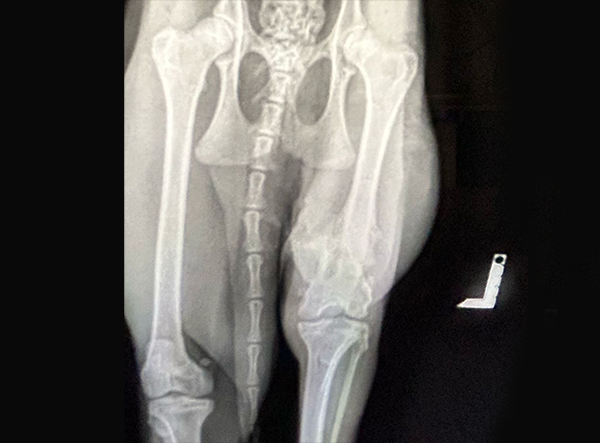

The femur fracture was surgically treated by Dr. Matan Or, using a 3.5 LeiLOX Locking Bridge Plate to provide stable fixation and support the healing process. The LeiLOX system is designed to offer reliable stability while minimizing soft tissue disruption, which is crucial for optimal recovery and a safe return to natural mobility. Its locking mechanism ensures strong fixation, and the bridging technique helps maintain blood supply to the bone, supporting natural bone regeneration.

Since the operation, the caracal has been recovering well, with stable post-op results and steady healing progress. Although a full recovery will take time, the outlook is very encouraging, and the wild cat is expected to gradually regain strength and mobility.

Implant Used:Â 3.5 LeiLOX Bridge Plate - Stainless Steel

System: LeiLOX Locking System

Manufacturer: Rita Leibinger Medical

Surgery by: Dr. Matan Or (Israel)